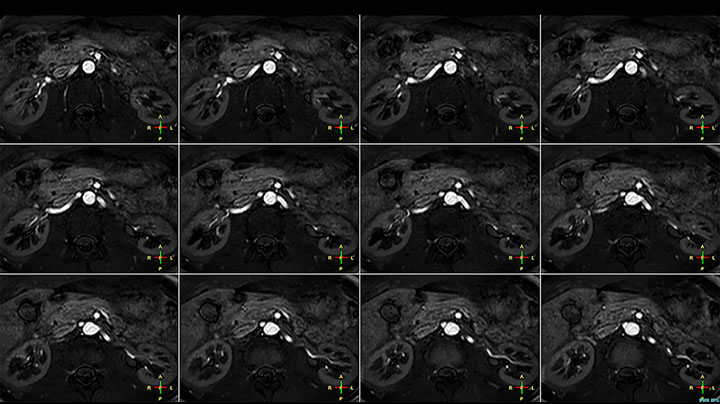

Although the area between the neck and the top of the lung is one of the most difficult areas for MRI, Prodiva 1.5T images show good quality in this 56-year-old male with Pancoast tumor on the right. mDIXON TFE images shows excellent fat suppression in the neck area and the DWI shows almost no distortion.

MRI of Pancoast tumor

Prodiva MRI pancoast tumor DWI, Seirei Mikatahara

Prodiva MRI pancoast tumor mDixon, Seirei Mikatahara

Prodiva MRI pancoast tumor dynamic, Seirei Mikatahara